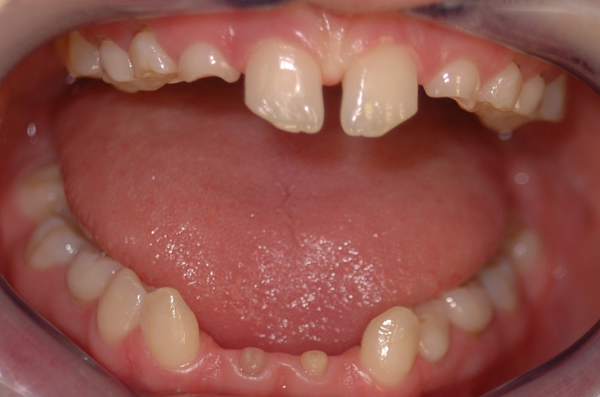

So vielfältig die Ursachen so weitreichend muss die Planung für die Implantologie sein. Alle Disziplinen der Zahnheilkunde sowie allgemeinmedizinische Aspekte sind zu betrachten. Ursachen (Nichtanlage, Unfall, Karies und Parodontitis)

Nichtanlage